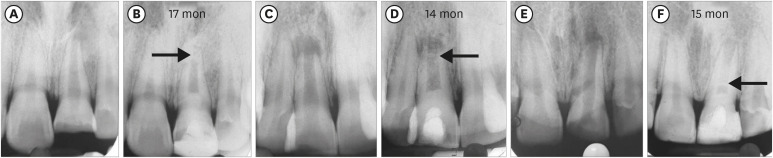

Figure 2 shows representative cases of each group BC, PRP, and PRF.

Figure 2

Intraoral periapical radiograph evaluation. (A, B) Blood clot group: No. 1: bone healing (BH)-3, apical closure (AC)-3, root wall thickness (RWT)-3, root length (RL)-1. (C, D) Platelet-rich plasma group: No. 1 (tooth #21): BH-3, AC-3, RWT-3, RL-3, No. 2 (tooth #22: mature): BH-3. Platelet-rich fibrin group: No. 1 (tooth #11): BH-3, AC-3, RWT-3, RL-2, No. 2 (tooth #12: mature): BH-3. Arrow indicates intracanal calcification.